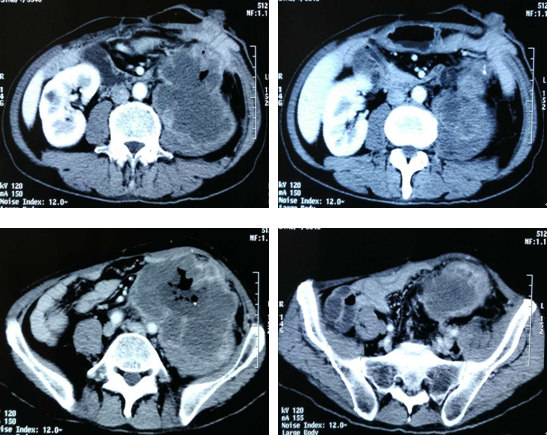

介入治疗前腹腔肿块巨大,>10厘米

两次介入治疗:

2017.6.12日

灌注化疗:雷替曲塞 2mg,奈达铂 60mg

2017.7.5日

灌注化疗+载药微球栓塞治疗

•灌注化疗:雷替曲塞 2mg

•Callispheres(300-500μm)可载药栓塞微球,载药伊立替康80mg